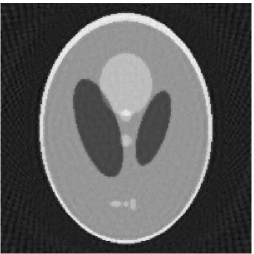

Noiseless projection data: Since the ghost in this phantom is invisible at 22 directions [10, 11], the reconstruction images usually suffer from artifacts. in our simulations, the projection data were collected in 112 and 82 directions: 90 and 60 with equal angle increments from to and 22 specified views in which the ghost is invisible [10]. Iteration procedures were terminated when for the noiseless projections.

The reconstruction images from the noiseless projection data were shown in the Fig. 6. For comparison, Table 3 present the iterations, MSE, Res and running time(RT) of different reconstruction results.

| Algorithm | TV-S | TV-PPS | TV-S | TV-PPS |

|---|---|---|---|---|

| projections | 112 | 112 | 82 | 82 |

| iterations | 24 | 19 | 33 | 32 |

| MSEs | 0.0056 | 0.0026 | 0.0108 | 0.0083 |

| RT(min) | 16.82 | 13.89 | 10.83 | 10.87 |

By comparing the images in Fig. 6, 7 and numbers in Table 3, 4, we can obtain the same conclusions that the proposed perturbation can not only improve qualities of reconstructed images, but also can accelerate the convergent speed. However, we can observe that the reconstruction images suffer from artifacts regardless of the classic and the proposed algorithm when the projections is inadequate.